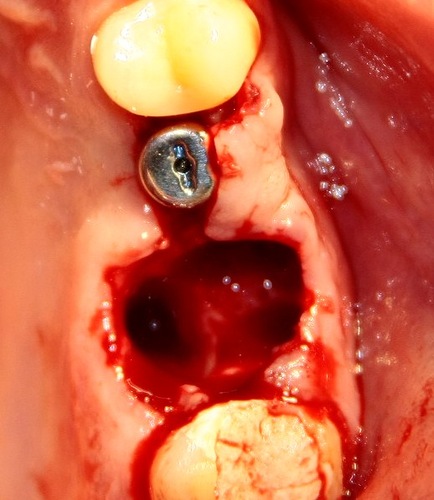

Ну ладно, удалили зуб. Что делать с лункой?

Правило третье — никаких выскабливаний, мы с вами не аборт делаем. Кюретаж необходим только в случае наличия явной гранулемы у корня зуба, либо если вы подозреваете, что по краям лунки (как правило, в пределах слизистой оболочки) остались мелкие кусочки зуба. Всё дело в том, что оставшиеся в лунке периодонтальные волокна — важный фактор удержания в ней кровяного сгустка. Если их выскоблить «до зеркального блеска», как написано в некоторых старых учебниках, то потом будем лечить альвеолит.

Правило четвертое — швы. В случае, если лунка зуба получилась большая, или для удаления зуба делались дополнительные разрезы — необходимо наложение швов. Идеальные материал для швов на лунки зубов — Vicryl или PGA, размером 3-0 или 4-0. Если предполагается одеть съемный протез зуба сразу после удаления, то можно использовать более тонкий шовный материал.

Наглухо ушиваются лунки только ретинированных зубов. Если коронковая часть зуба видна хотя бы частично, герметичные швы могут привести к осложениям: инфицированию области лунки и развитию абсцесса.

Некоторые коллеги до сих пор используют йодоформные турунды для тампонады лунки. Вопрос к ним: «Для чего?». Йодоформ из турунды растворяется и вымывается через несколько часов, после чего сама турунда становится рассадником инфекции. Она никак не способствует заживлению костной раны, а после ее удаления\выпадения образуется т. н. «сухая лунка». Ну и пахнет она отвратительно.

Обычно в лунку после удаления зуба я помещаю Neocones (Septodont). При его отсутствии можно использовать Alveogyl или «Альвостаз». Нужно ли помещать в лунку какие-нибудь остеопластические материалы? Об этом почитайте в статье о немедленной имплантации.